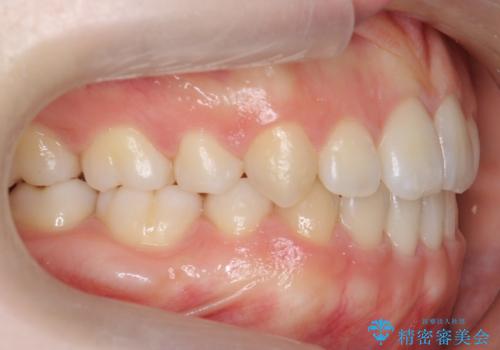

[ マウスピース矯正 ] 長期海外出張中に矯正治療を行いたい